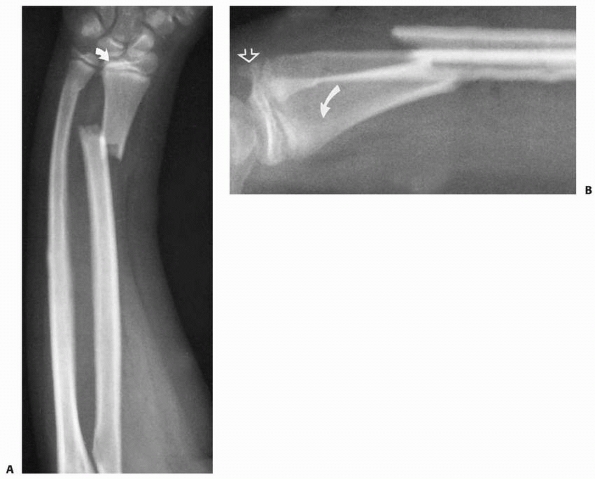

fracture type and deformity. The Salter-Harris system is the basis for

metaphyseal fragment is evident on the lateral view (Fig. 9-8).

Salter-Harris type I fractures also usually displace dorsally. Volar

common (Fig. 9-9). Nondisplaced Salter-Harris type I fractures may be indicated only by a displaced pronator fat pad sign (Fig. 9-10)198,253 or tenderness over the involved physis.8,181 A scaphoid fat pad sign may indicate a scaphoid fracture (Fig. 9-11). If the acute fracture is unrecognized, a late-appearing periosteal reaction may indicate the fracture.